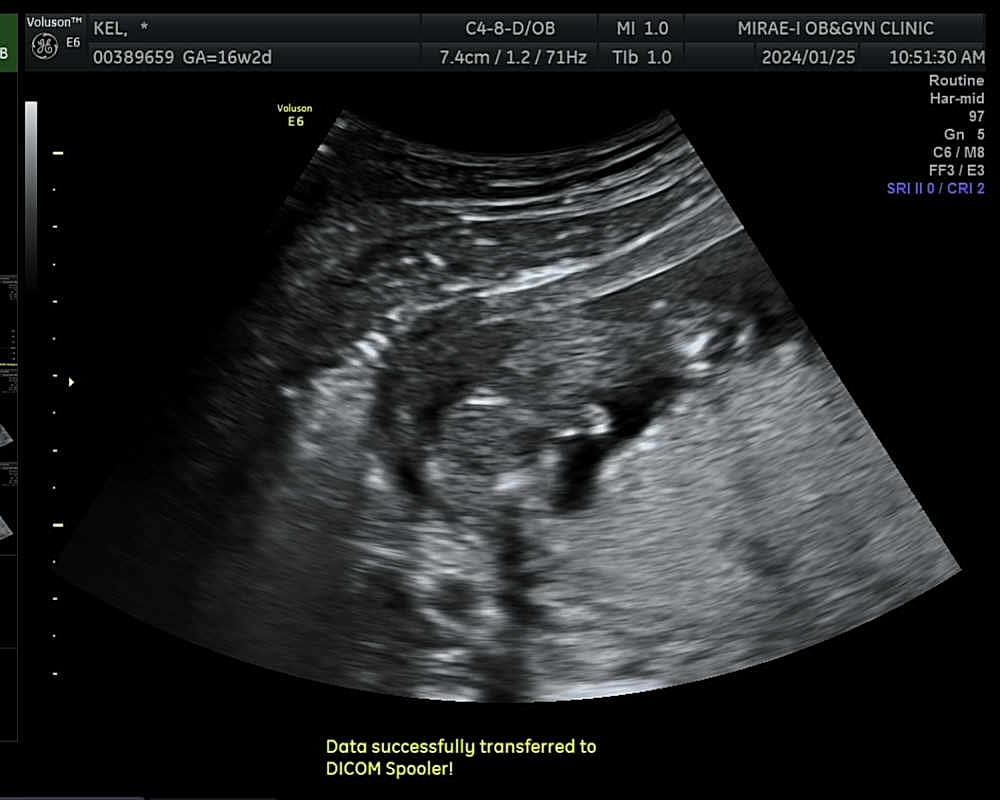

초음파 각도로는 딸같다는 소리들엇지만! 쪼리는 아들이였습니다 🦖🦖💙 저는 아들를 원했고 딸바보를 꿈꾸던 남편은ㅋㅋㅋㅋㅋㅋㅋ지금 좌절감에..😂 네이버에 성별 바뀔가능성을 처보면서 현실부정하고잇는데 그 모습이 얼마나 웃기고 기엽던지 친한친구가 태몽으로 엄청 큰뱀🐍꿈을 꿧다했는데 그게 용이였나 ? 그래서 아들인가~? 태몽도 신기하고 내 뱃속에 아들이 있다는것듀도 신기하고 오늘 하루 설레는 하루가될것같아요 ෆ